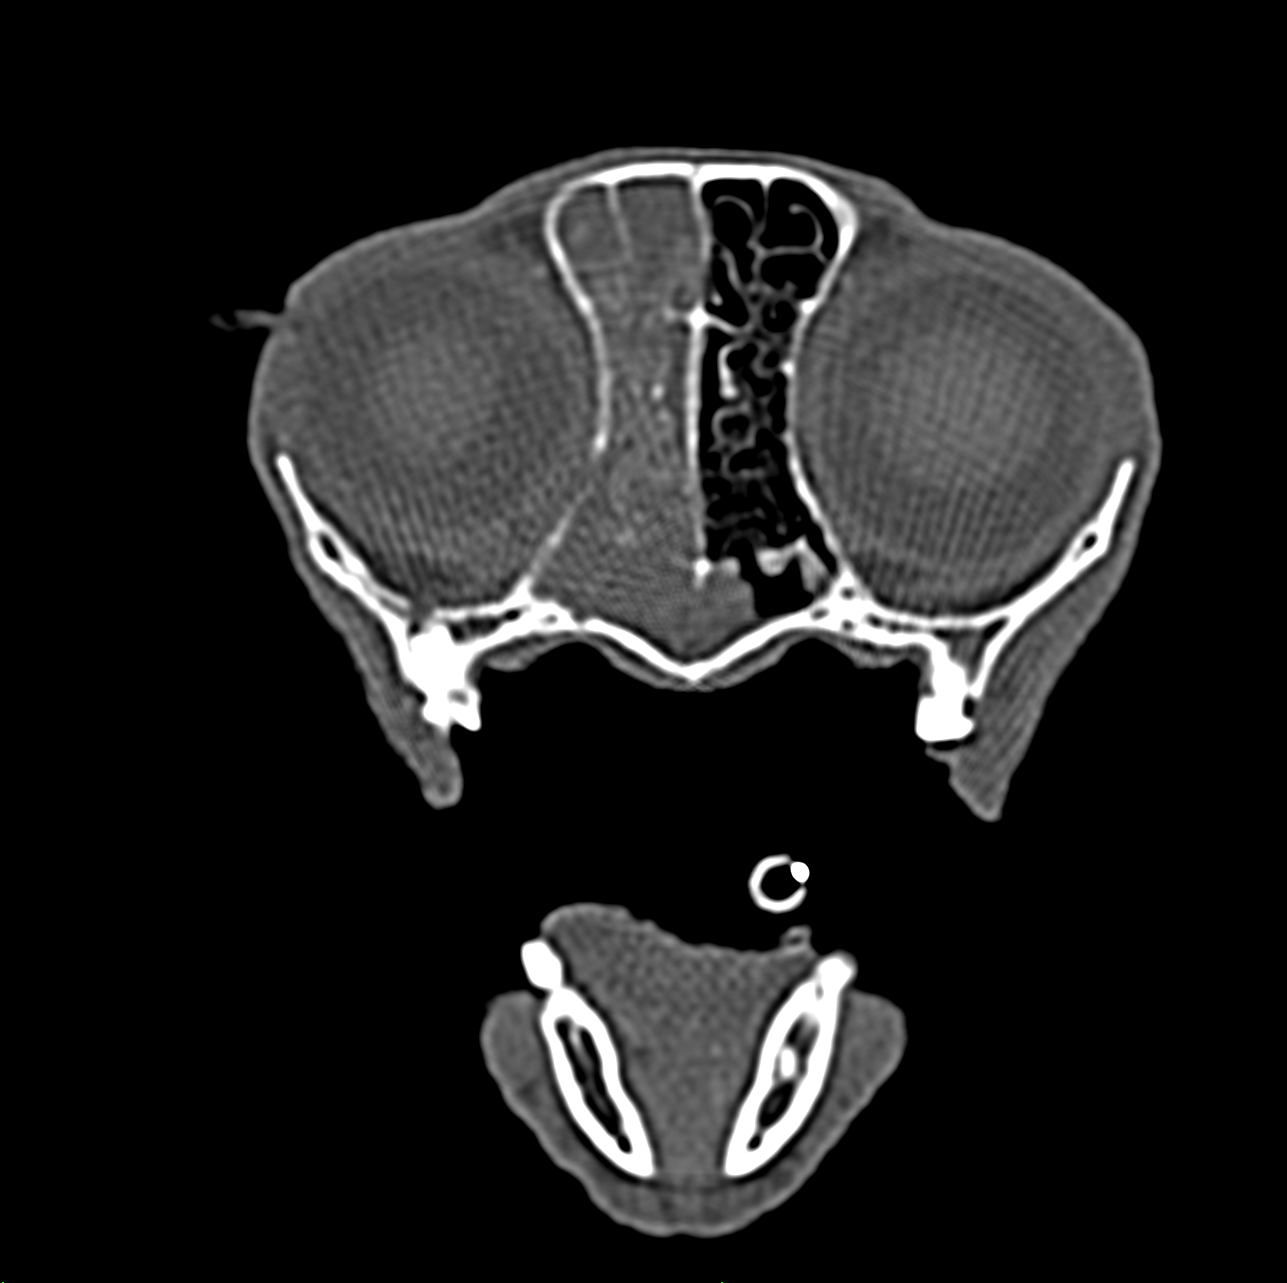

Ab wann ist eine Trächtigkeitsuntersuchung mit einem Röntgengerät möglich?

Eine Röntgenaufnahme des Bauchraumes zum Nachweis einer Trächtigkeit ist ab dem 42. Tag möglich, aussagekräftiger ist sie aber ab dem 50. Tag der Trächtigkeit, da zu diesem Zeitpunkt die Verknöcherung der fetalen Skelette weiter fortgeschritten ist. Sie dient als Vorsorgeuntersuchung in der Trächtigkeit zu Bestimmung der Fetenanzahl, wobei dies bei sehr großen Würfen teilweise schwierig sein kann. Die Röntgenaufnahmen schädigen die Feten nicht, da die Organentwicklung mit der Embyrogenese um den 30. Tag bei der Hündin abgeschlossen ist.